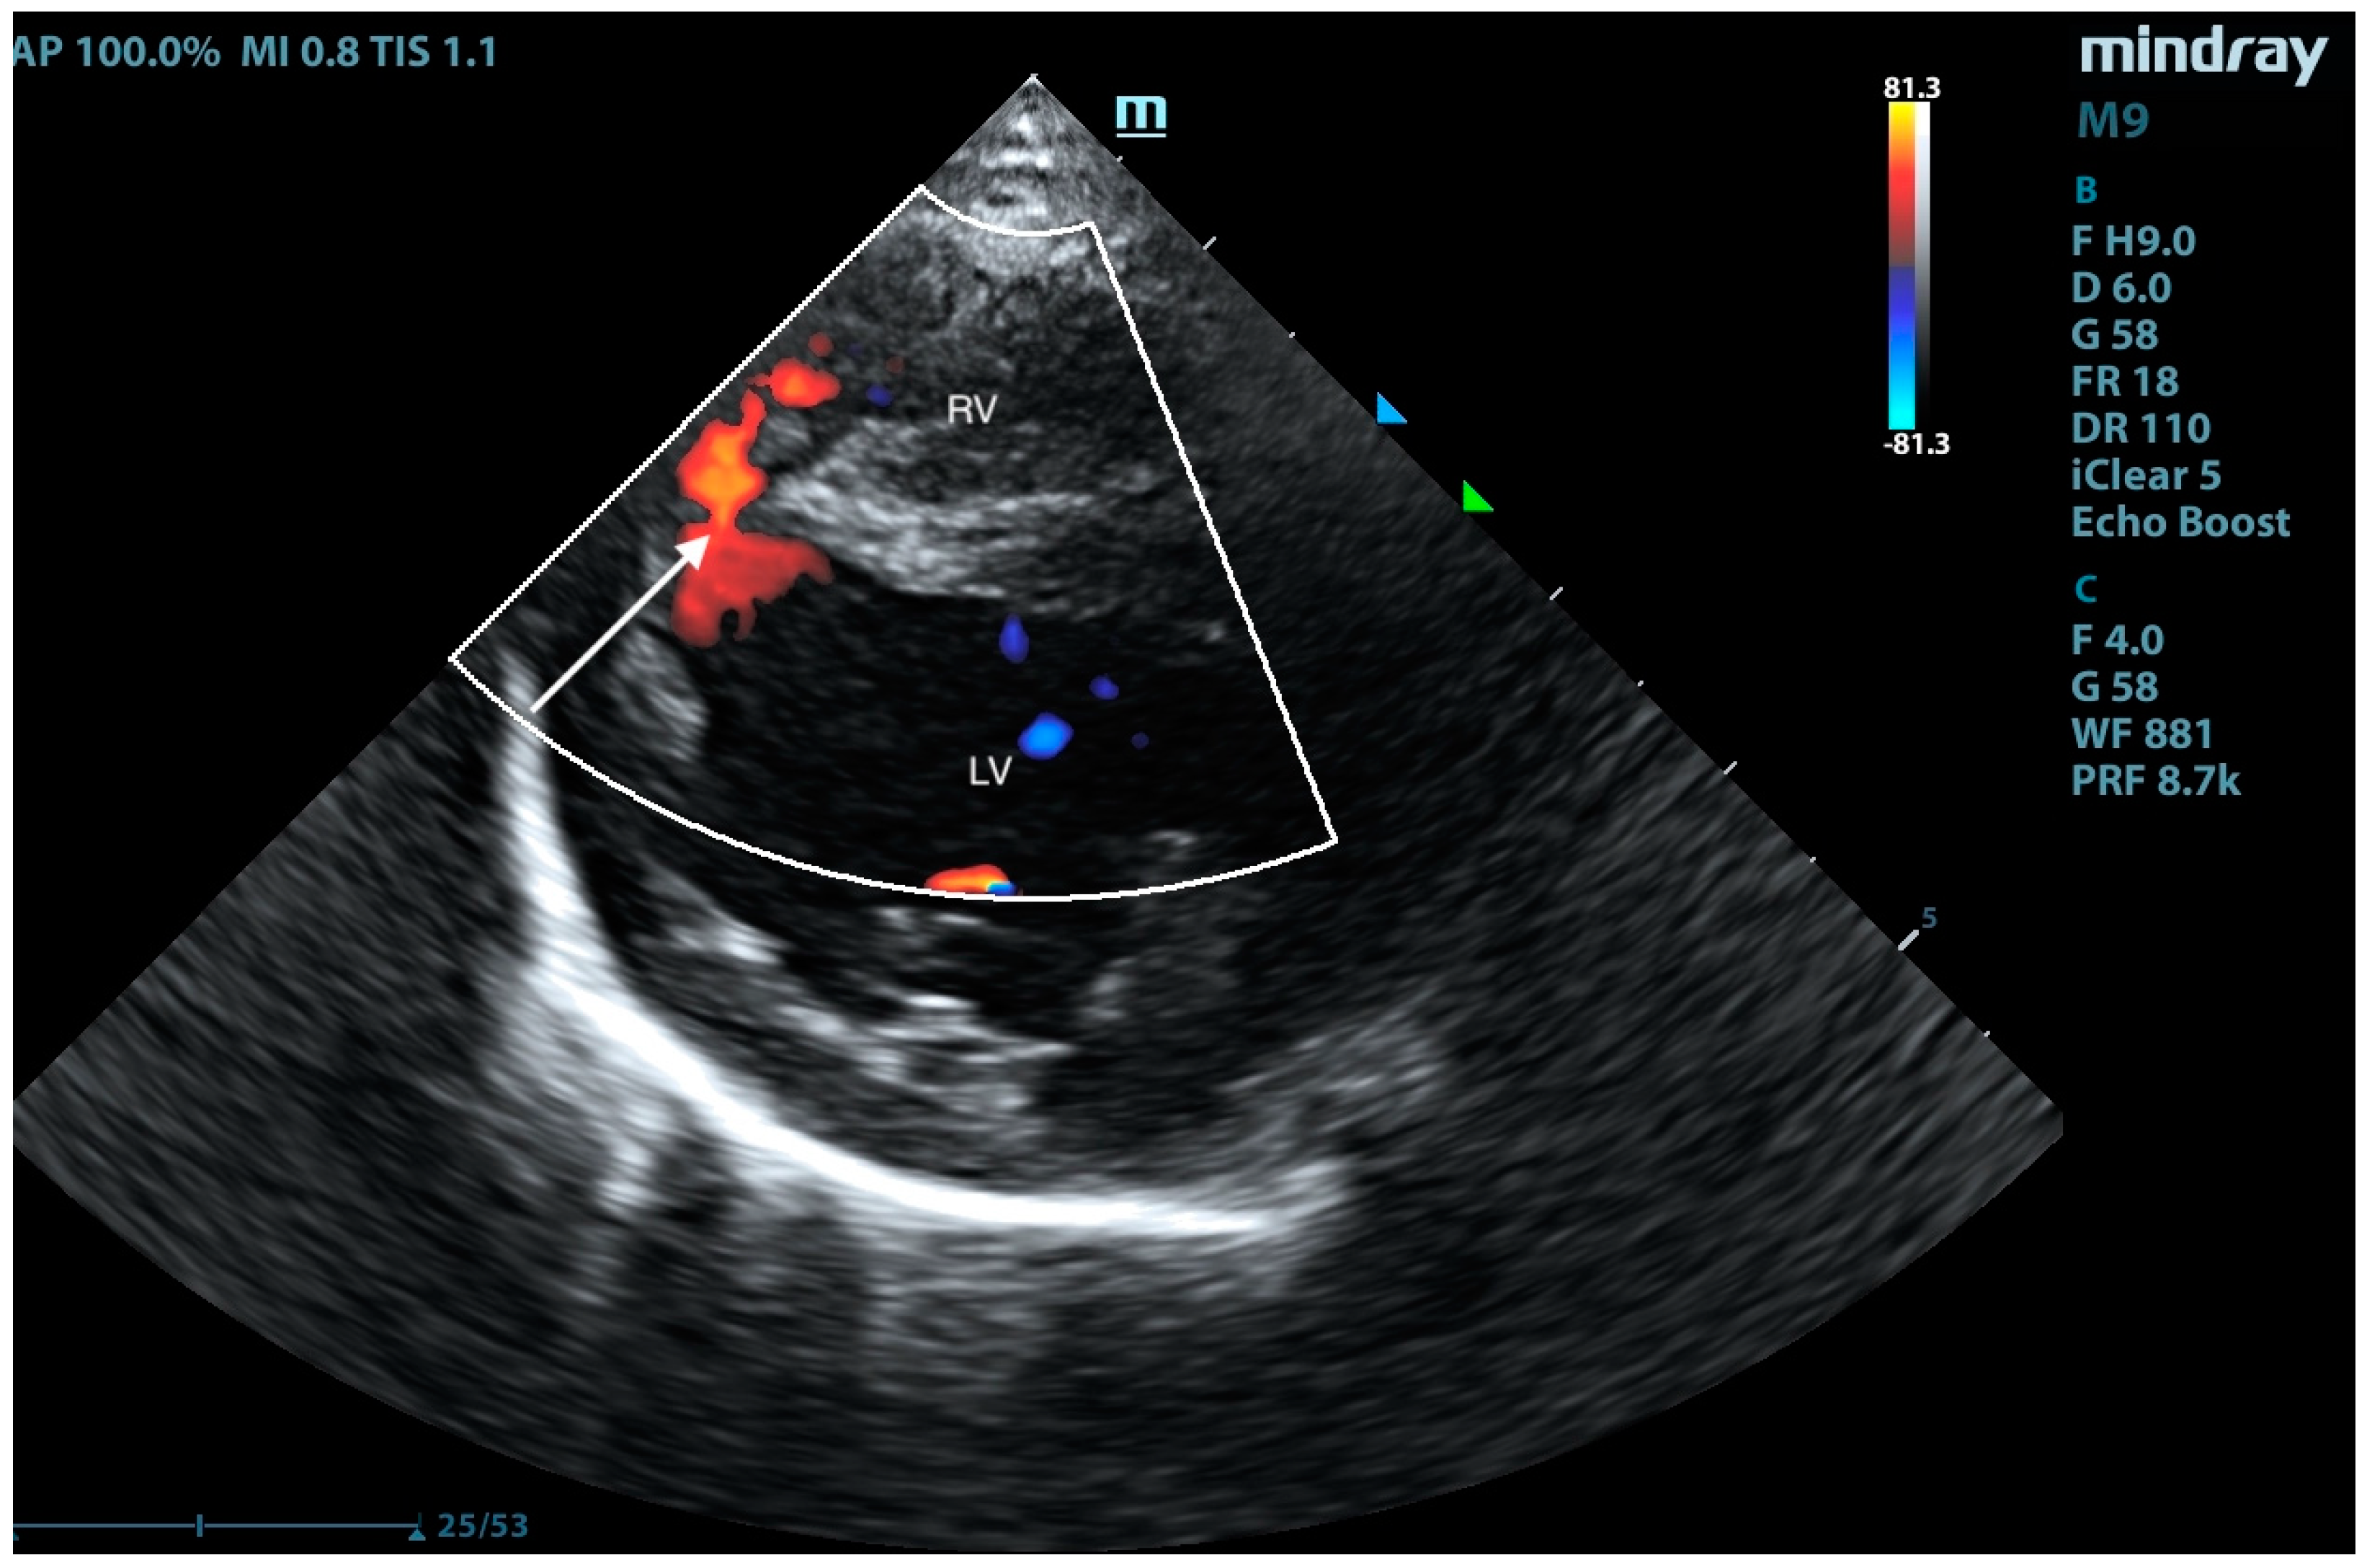

2. Case Presentation